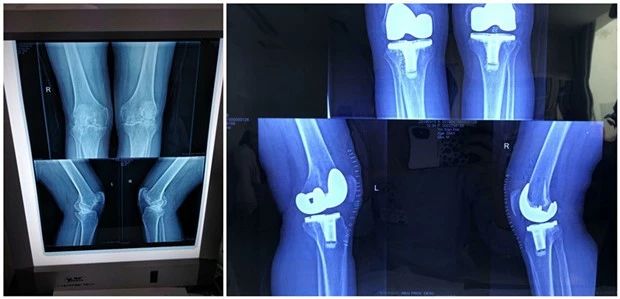

术前 术后

今年54岁的殷某,因患骨性关节炎多年,双膝关节面严重破坏,双腿屈曲挛缩畸形,疼痛难忍,行走功能障碍,影响正常生活,需行人工膝关节置换术治疗,家人经多方了解,综合比较,最后决定在我科手术。手术前,贾主任带领其团队经过充分评估,为其设计出最佳的手术方案;责任护士依据膝关节置换术“一病一品”全程护理指导流程为其进行详细宣教指导,患者在腰硬联合麻醉下顺利完成“双膝人工全膝关节置换术”。

成功的手术+系统的康复=满意的效果。积极有效的康复可以防止患者关节局部组织挛缩、粘连和僵硬,帮助患者恢复肌力,增加关节稳定性,改善关节功能,改善下肢的负重能力及步态,提高生存生活质量。手术后,医护人员为患者进行了全面详细的评估,制定了个性化的康复方案,康复护士每天耐心指导患者功能锻炼相关动作和注意事项,患者积极配合,努力锻练,情况一天天好转,术前行走困难的他,术后重建关节功能,现在可以自己在病房走廊里稳步走来走去,恢复正常生活。